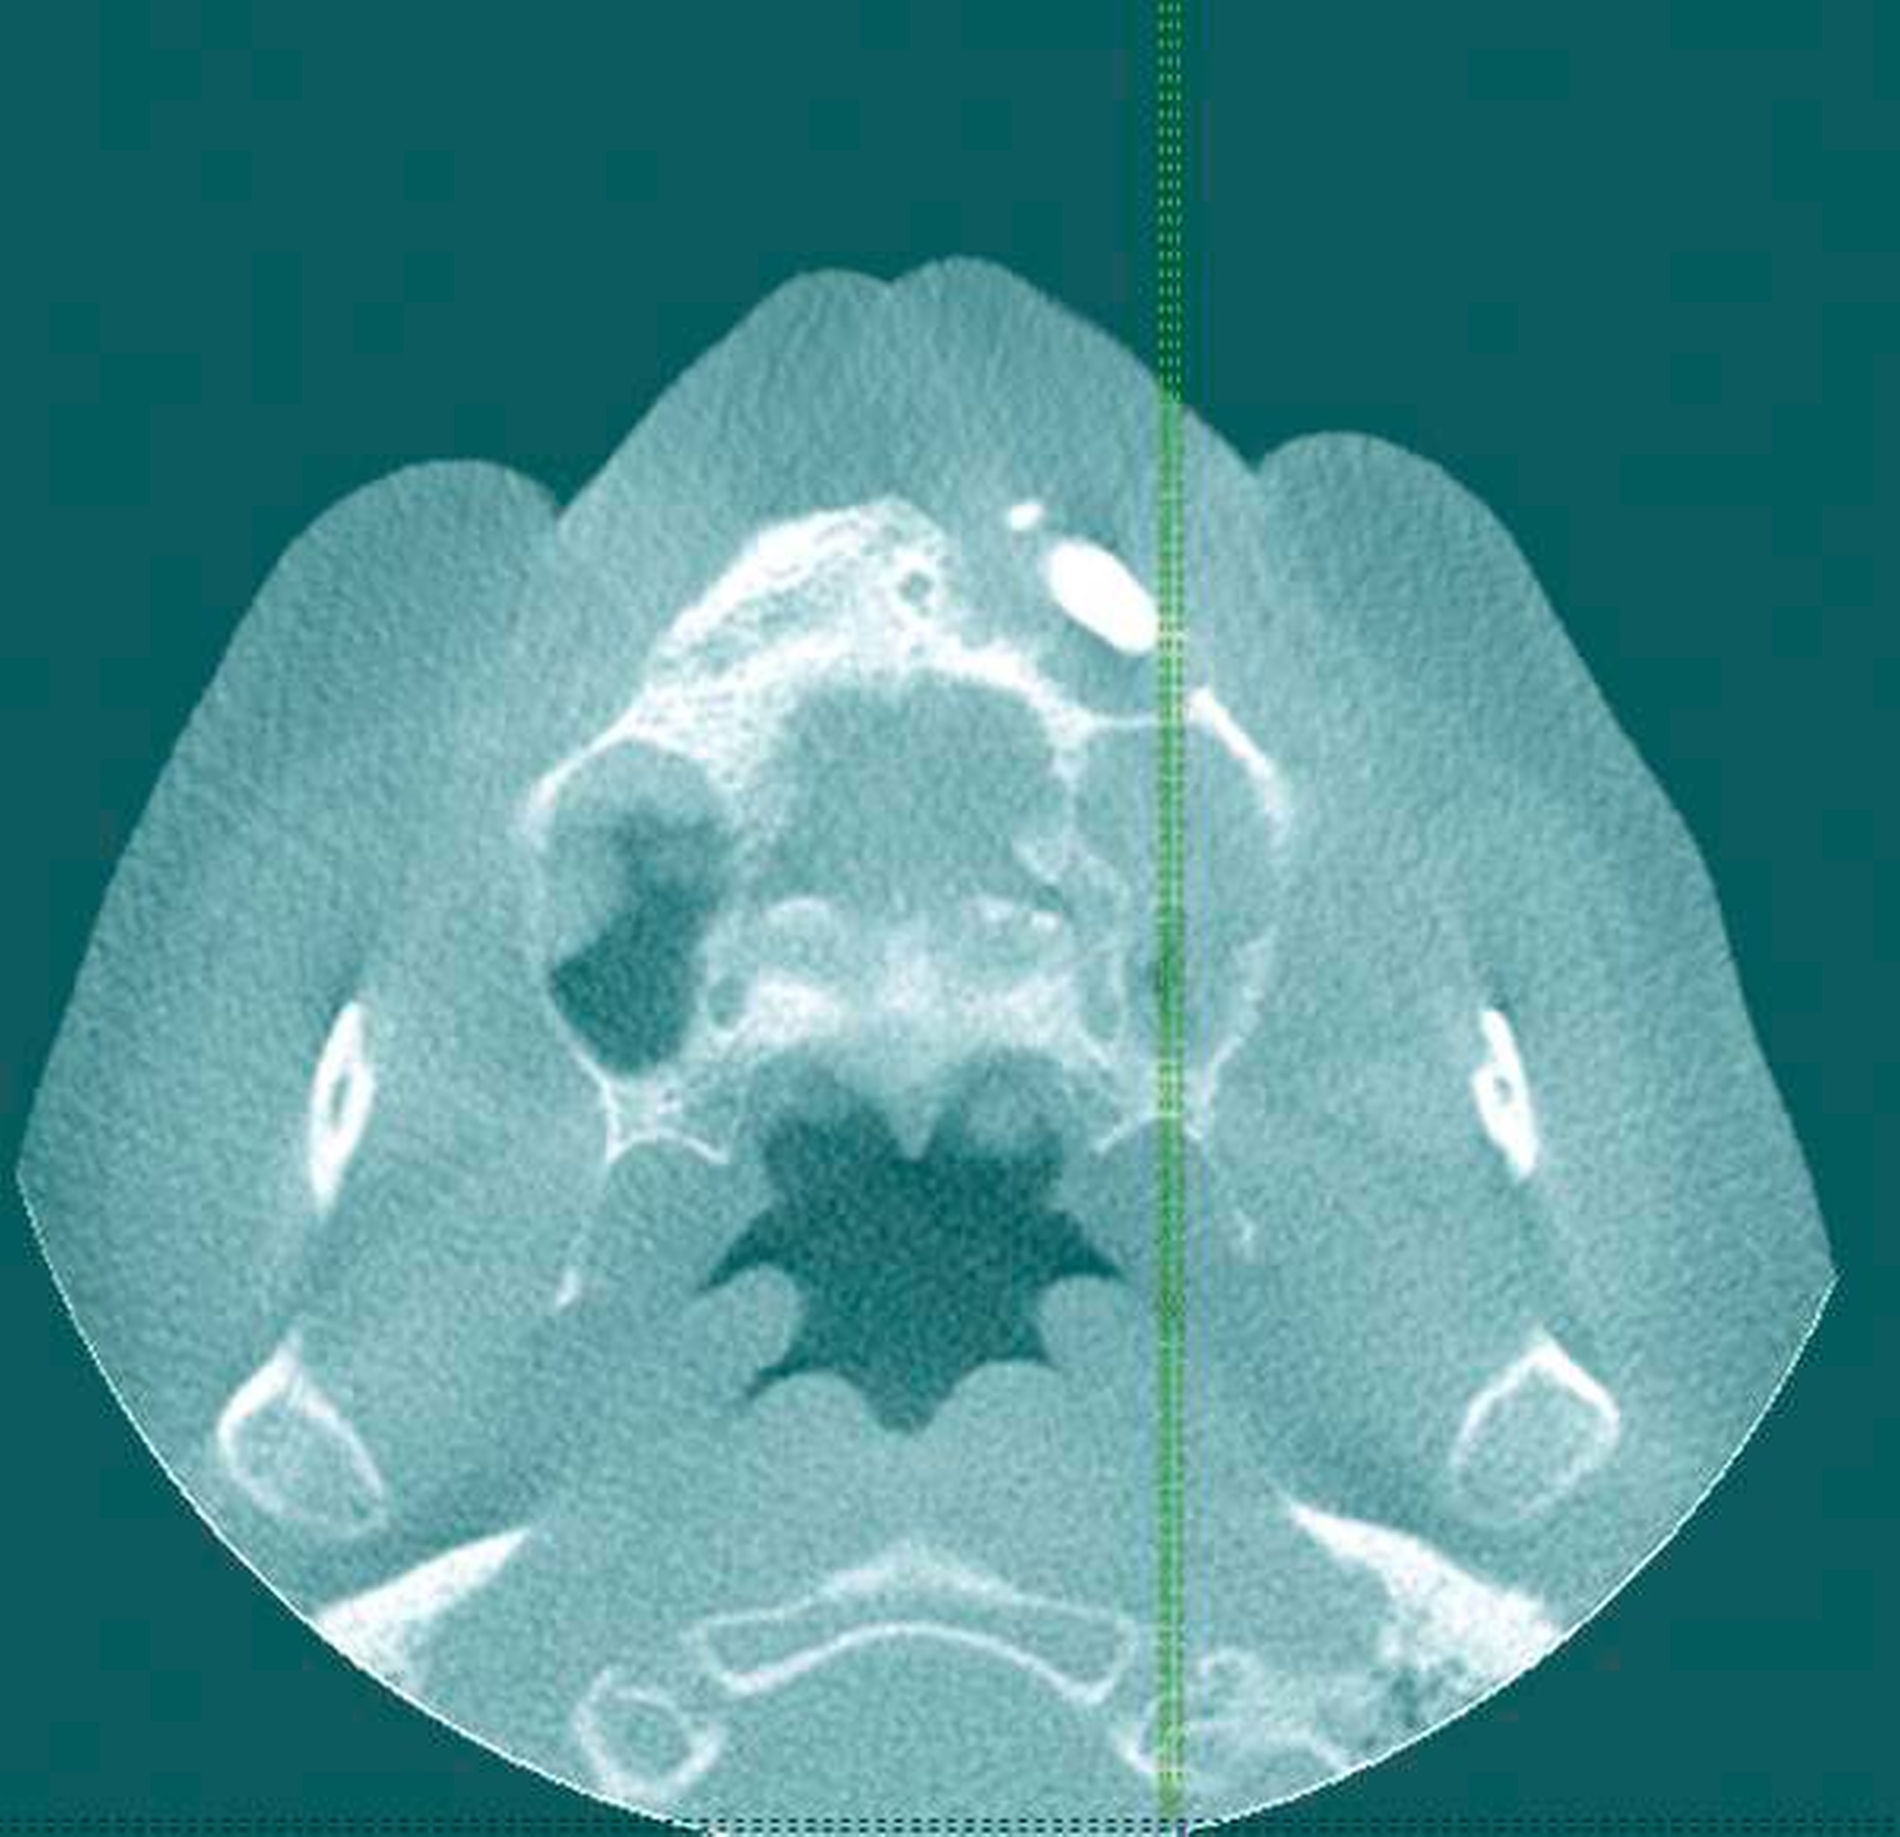

In der durchgeführten radiologischen Diagnostik zeigten sich ausgeprägte Parodontopathien mit Verdacht auf eine BRONJ bei gut begrenzter radiologischer Aufhellung mit Kieferhöhlenbeteilung (Abbildungen 3 bis 5). Unter der Verdachtsdiagnose einer BRONJ wurde somit die Indikation zur Zahnsanierung mit Exzision der pathologischen Veränderung im Oberkiefer gestellt. Nach Entfernung der gelockerten Brücke zusammen mit den die Brücke tragenden Zähnen zeigten sich große Mengen harten, anhaftenden Gewebes (Abbildung 6); der unter dem Befund liegende Knochen stellte sich klinisch als vital und ohne Anzeichen einer Nekrose dar.

Morphologisch zeigt sich der befallene Knochen deutlich verändert und gräulich bis gelblich verfärbt. In der radiologischen Bildgebung kann sich die BRONJ insbesondere zu Beginn noch unauffällig darstellen. In späteren Stadien kann es zur Aufhebung der kortikospongiösen Struktur mit Spongiosasklerose und periostaler Auflagerung kommen. Das typische Auftreten nebeneinander liegender röntgenologischer Aufhellung und Verschattung ebenso wie die Sequestrierung der ossären Strukturen oder das Vorkommen pathologischer Frakturen erhärten den Verdacht auf eine Kiefernekrose. Therapeutisch steht die chirurgische Sanierung mit dichtem Wundverschluss oder – im Fall ausgedehnter Defekte – die Kontinuitätsresektion mit anschließender Rekonstruktion im Vordergrund. Konservativ kann ein Therapieversuch mittels systemischer Antibiotikagabe erfolgen [Kämmerer, 2013; Gujer, 2013]. Die Gruppe in die Differenzialdiagnostik einzubeziehender, sich klinisch-radiologisch ähnlich präsentierender Befunde umfasst Erkrankungen aus dem Bereich der malignen wie der benignen Knochentumore und tumorähnliche Veränderungen (Tabelle 1).